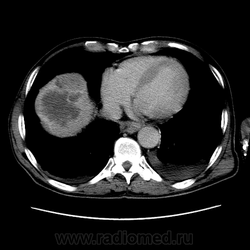

Печень. Процесс в средостении, бр.пол., забр.пр-ве. МСКТ.

Здравствуйте, коллеги! Мужчина около 70 лет. Жалобы: слабость, утомляемость около 3х месяцев, чувство тяжести на желудке после еды. Анамнез: онко не было. С вышеописанными жалобами обратился ко врачу, сделали ФГЭДС - признаки гастродуоденита, по биопсии - N. В течение 2х последних недель существенно похудел и начал желтеть. Выполнена МСКТ

А как насчет холангиокарциномы с тромбозом воротной вены и мтс в средостение, лимфоузлы брюшной полости и забрюшинного пр-ва?

Я - за.

Внимательно пересмотрел, признаков характерных для ГЦР не нашел (кроме тромбоза). Согласен с холангиокарциномой, ещё бы отсроченную фазу, для печени минут через 12-15 .

Для ГЦР характерно

1. Гиперденсивность, в артериальную фазу  всей опухолевой массы (опухоль хорошо васкуляризирована)

2. Гиподенсивность, в портальную фазу (быстрое вымивание, опять же обусловлено васкуляризацией)

3.Тромбоз портальной вены.

Для холангиокарциномы характерно гиперденсивность, в отсроченную фазу, за счет аффинитета к контрастному веществу.